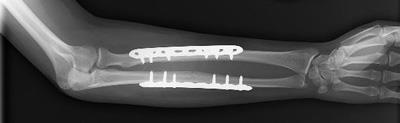

Internal fixation of forearm fracture

In this X-ray, the broken bones of the forearm are held in position by plates and screws while they heal.